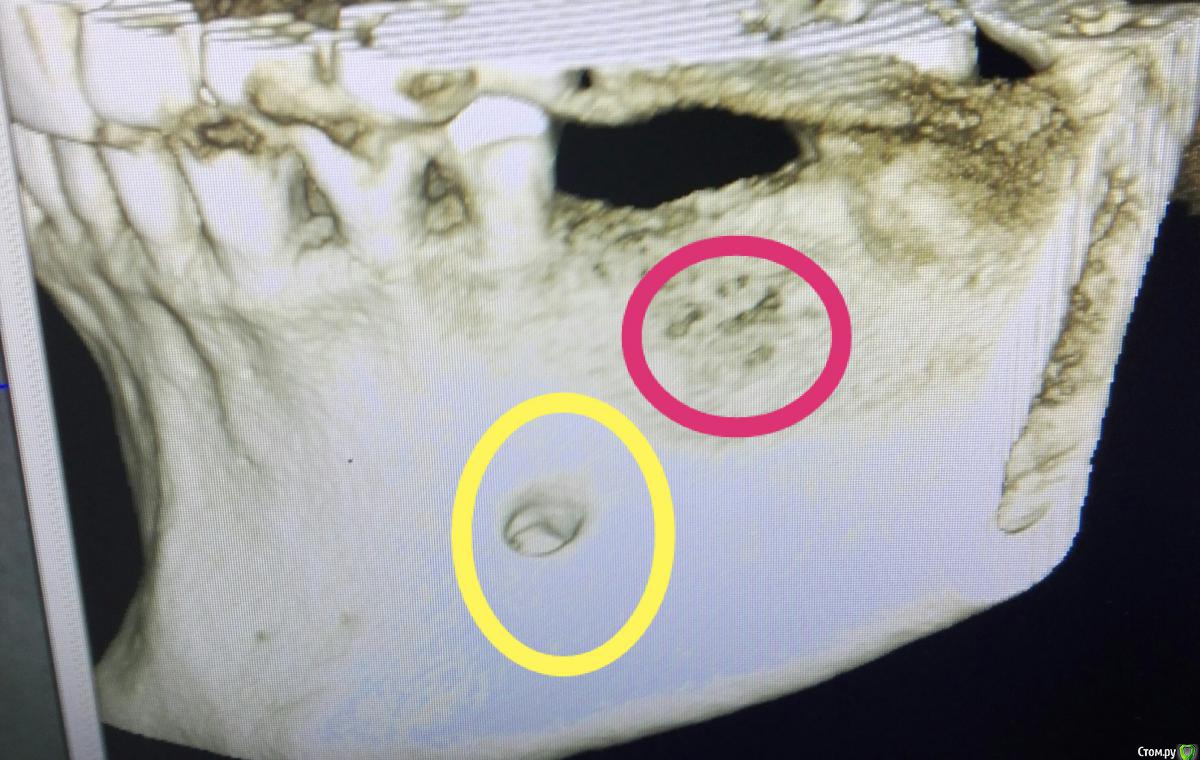

karasov Опубликовано 20 октября, 2016 Поделиться Опубликовано 20 октября, 2016 (изменено) В области 36 работал с ламиной. Наткнулся на нерв. Причем два. Один обошел , второй нет. Что ждать?на кт ееееле заметны Изменено 20 октября, 2016 пользователем karasov Ссылка на комментарий

kriokov Опубликовано 21 октября, 2016 Поделиться Опубликовано 21 октября, 2016 Наткнулся на нерв. не похож на нерв. имхо. Ссылка на комментарий

karasov Опубликовано 21 октября, 2016 Поделиться Опубликовано 21 октября, 2016 не похож на нерв. имхо.По кт есть однозначно связь с нижним альвеолярным. Визуально на сосуд не похоже Ссылка на комментарий

karasov Опубликовано 21 октября, 2016 Поделиться Опубликовано 21 октября, 2016 Слева был, справа есть Ссылка на комментарий

karasov Опубликовано 21 октября, 2016 Поделиться Опубликовано 21 октября, 2016 Обычно встречается первый тип, но у части населения бывает и второй..Или третий Ссылка на комментарий

koreandr Опубликовано 25 октября, 2016 Поделиться Опубликовано 25 октября, 2016 Это лунка заживает так Ссылка на комментарий

karasov Опубликовано 2 ноября, 2016 Поделиться Опубликовано 2 ноября, 2016 Это лунка заживает такне думаю,тк на кт с двух сторон Ссылка на комментарий